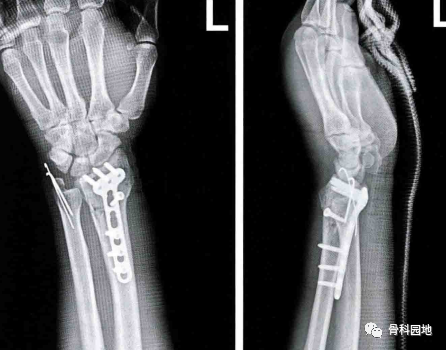

桡骨远端骨折是常见骨折,多数通过改良的Henry人路行掌侧钢板固定获得满意疗效。

下面就总结一下桡骨远端骨折掌侧入路一些手术中的经验与技巧。

一:当外侧柱被累及时,需要松解肱桡肌止点,否则其牵拉作用可能造成桡骨远端外侧柱高度复位困难。且当掌侧固定物不能为移位的桡骨茎突提供稳定时,也建议松解肱桡肌止点,并辅以小的桡侧钢板固定。

二:在复位关节远端骨折块时,不要打开腕关节囊。否则会导致桡腕关节不稳及术后僵硬。

三:骨折的复位与固定顺序取决于骨折块的位置与大小。

先复位最大的骨块以及粉碎程度最轻的骨折块。依次固定余下的骨折块。

克氏针可以用来帮助最初的复位,如果钢针妨碍了钢板的放置,可以将其从腕背侧引出。

四:确定钢针或螺钉没进关节。腕关节尺偏20°透视检查螺钉位置,避免螺钉进入关节。螺钉过长时只要穿出对侧皮质超过1~2mm就会刺激伸肌腱。

五:远端螺钉置于软骨下骨可以增强内固定的稳定性,特别是老年骨质疏松患者。

六:原位缝合旋前方肌,可以覆盖内固定物,防止对屈肌腱的刺激,减少腕关节活动痛等手术并发症。

七:Barton骨折:掌侧剪切造成的桡腕关节骨折脱位,往往有两个以上的骨块,掌尺侧骨块往往较小,如果没有获得充分固定,桡腕关节面之间失去有效支撑,造成桡腕关节伴随骨块半脱位。

八:老年骨质疏松患者的桡骨远端骨折应该考虑到背侧皮质粉碎,掌侧内置物向远端推举移位的远端掌侧骨块,可能造成背侧骨块的移位,失去正常的掌倾角。

九:如果月骨面掌侧骨块的骨性支撑不足,为避免骨块翻转、可采用缝合固定。

十:桡骨远端骨折合并尺骨茎突骨折的处理:

桡骨骨折固定后,应当在旋前位、中立位和旋后位进行应力试验,检查下尺桡关节的稳定性;当合并尺骨茎突骨折,特别是尺骨茎突基底部骨折时,桡骨远端骨折内固定后,检查下尺桡关节仍存在不稳,说明尺侧柱伴随严重损伤造成尺侧不稳,需行内固定恢复其稳定性。

如果没有合并尺骨远端骨折,桡骨远端骨折固定后,检查下尺桡关节仍出现不稳,说明稳定下尺桡关节的韧带损伤。术后应采用超肘关节制动腕关节和前臂4周,或同时经尺、桡骨横行穿针临时固定,或切开修复三角纤维软骨复合体。